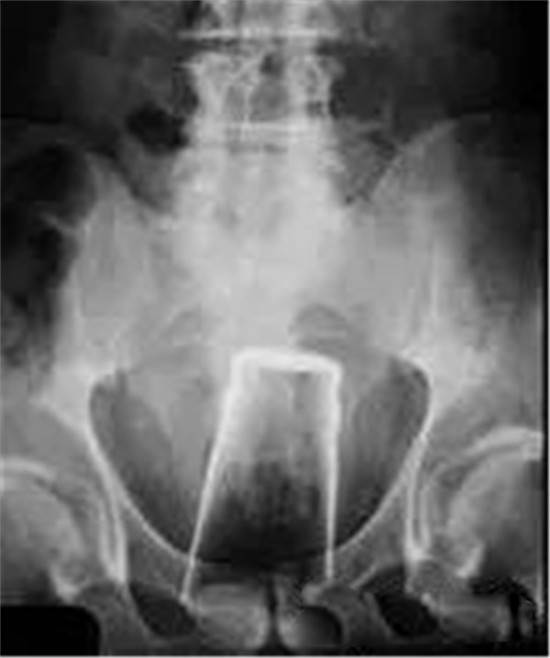

这是一个啤酒瓶。男性。

上面是一个啤酒瓶在大肠里。病人是男性。这是常见的肛门内异物。

这种情况,往往只要给病人打上全身麻醉,肛门松弛后,就可以用卵圆钳经过肛门把啤酒瓶拉出来。